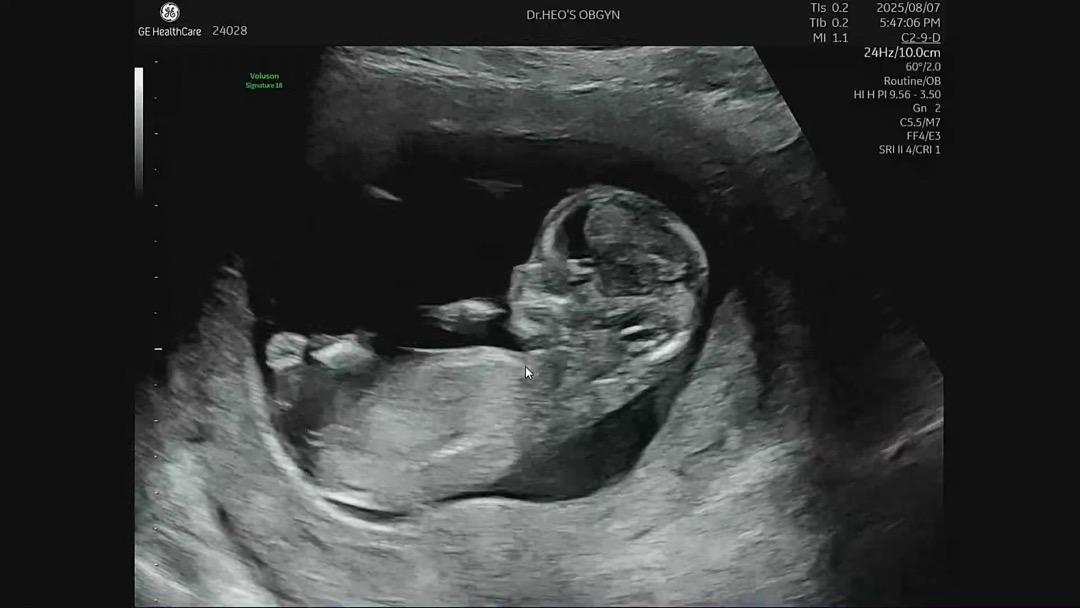

12주2일 각도법봐주세요!

오늘보고왔는데 영상은안올라가네오 이걸로 알수있을까요